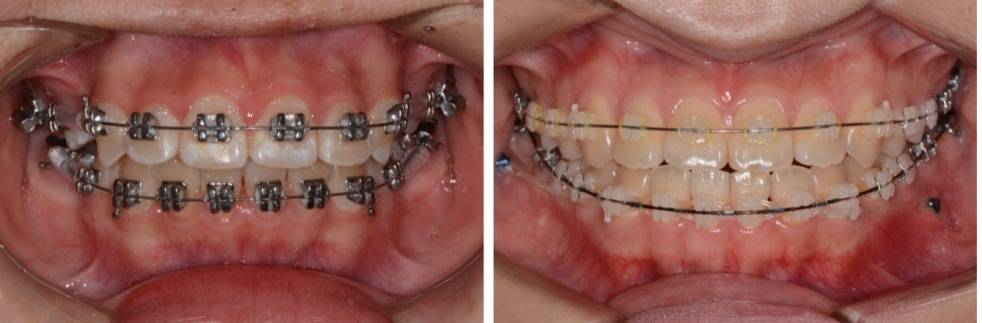

正 畸-正颌联合治疗矫治不对称牙颌面畸形

正畸的基本知识、 特殊情况的正畸、牙套的选择、正畸的关注事项和可能的并发症、正畸-正颌联合治疗、正畸治疗中的常见问题、正畸治疗结束、复发及保持。